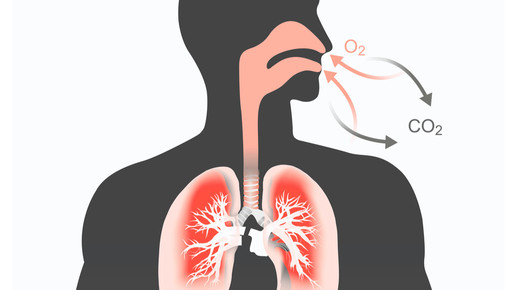

Häufig ist die Rede von den oberen und unteren Atemwegen. Doch eigentlich sind die gesamten Atemwege sowohl anatomisch wie auch funktionell miteinander verbunden – Nase und Lunge bilden ein System. Zu Beginn einer Erkältung ist meist der obere Teil der Atemwege betroffen – im weiteren Verlauf können sich dich Keime mitunter in allen Teilen der United Airways ausbreiten.

Eine virale Erkältung geht anfänglich meist mit Schnupfen einher. Das Nasensekret wird mit Fortschreiten des Infekts zäher, durch die zugeschwollene Nase ist die Belüftung der Nebenhöhlen nicht mehr sichergestellt. Der viskose Schleim bildet zudem einen optimalen Nährboden für Bakterien – diese können sich ungestört vermehren und ausbreiten. Da die Atemwege miteinander verbunden sind, können sich die Krankheitserreger ausbreiten und mitunter verlagern. Die Folge: Nach einer Nasennebenhöhlenentzündung tritt Husten auf – es kommt zum Etagenwechsel. Der Wechsel kann auch umgekehrt stattfinden: Bei einer Bronchitis können die Erreger nach oben wandern und den Nasen- oder Rachenbereich befallen.